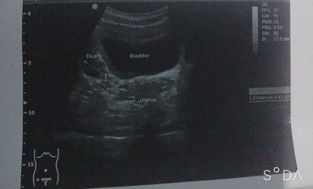

ขอความคิดเห็นคำปรึกษาจากคุณแม่หน่อยค่ะ ภาพอัลตร้าซาวน์ภาพนี้ ตั้งครรภ์ไหมค่ะ. หรือว่าไม่ตั้งครรภ์